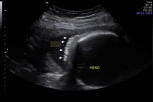

Lekari su na kraju utvrdili da je beba Renli rođena sa anoftalmijom, genetskim stanjem koje uzrokuje da se bebe rađaju bez očnog tkiva ili optičkih nerava. Renli je takođe rođena bez kortizola, a kombinacija svih ovih faktora značila je da su joj oči bile zatvorene, piše "San".

- Poremećaj PRR-12 ima širok spektar uticaja na pacijente. Neki pacijenti sa istom promenom gena imaju jedno oko i ono može biti potpuno odsutno kao u njenom slučaju, ili može biti samo manje, a u ovom slučaju su zahvaćena oba oka - tvrdi doktor.